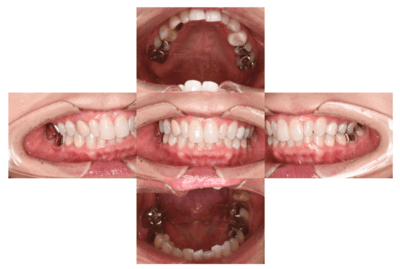

初診時の口腔内

説明:

初診時の口腔内です。かぶせ物があり、一見虫歯とはわからないです。

初診時のパノラマ

初診時のパノラマです。左下の一番奥の歯が虫歯になっているのがわかります。